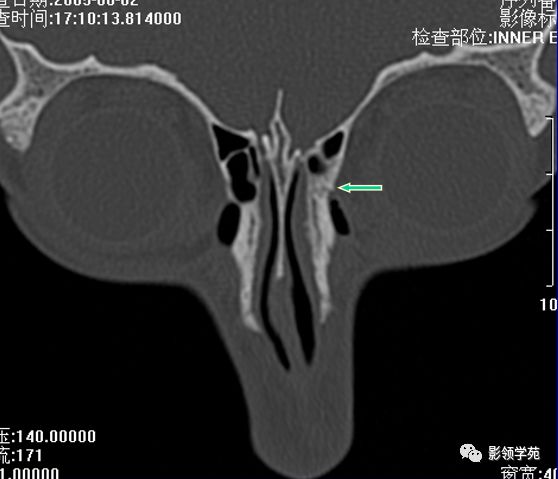

双侧鼻骨骨折

鼻中隔骨折